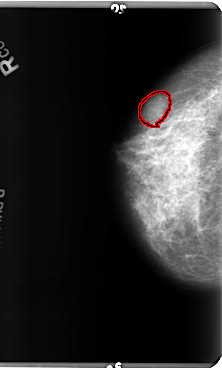

B_3156_1.RIGHT_MLO

RIGHT_CC LINES 4800 PIXELS_PER_LINE 2880 BITS_PER_PIXEL 12 RESOLUTION 50 OVERLAY

FILE: B_3156_1.RIGHT_CC.OVERLAY

TOTAL_ABNORMALITIES 1

ABNORMALITY 1

LESION_TYPE MASS SHAPE OVAL MARGINS CIRCUMSCRIBED-OBSCURED-ILL_DEFINED

ASSESSMENT 4

SUBTLETY 3

PATHOLOGY BENIGN

TOTAL_OUTLINES 1

BOUNDARY